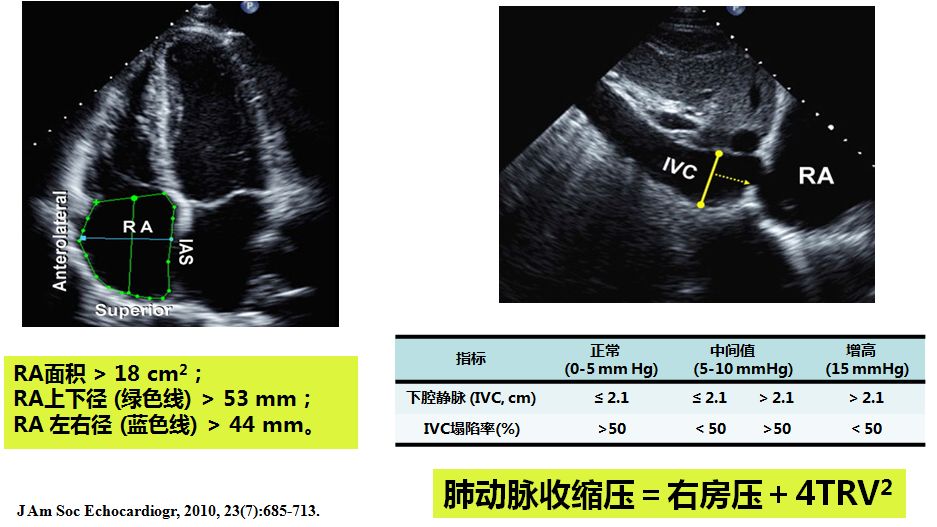

➤ 肺动脉压力超声评估

➤ 右房压估测